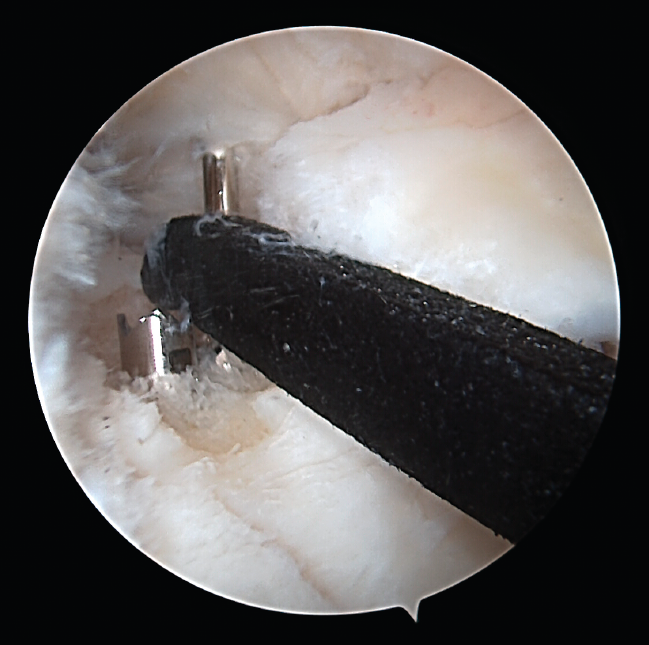

Standard anteromedial and anterolateral portals were used. Once the rupture was identified, the bed of the meniscal root was prepared with an arthroscopic drill, removing the cartilage and leaving a freshened bone base. Using the corresponding guides (Figure 5), two 2.8-mm tunnels were made for passing two number 2 FiberStick® sutures (Arthrex, Inc., Naples, Florida, USA) through one of them. After suturing the meniscus with two simple stitches using a FirstPass® suture passer (Smith & Nephew, Inc., Massachusetts, USA), they were recovered through the other tunnel and knotted onto themselves at the anterior cortical layer of the tibia.

Figure 5. Adaptation of the guide in the surgical field.

Figure 6. View from the anterolateral portal of the intraarticular positioning of the guide and the intraarticular exit of the tunnels at the footprint of the posterior root of the internal meniscus of a right knee.

One of the patients in the standard guide group required modification of the perforation secondary to intraarticular exit of the Kirschner wire in a position different from that planned, due to positioning difficulties caused by the existence of a narrow intercondylar groove and prominent spines. The 3D printed guides adapted on both supports to the bone surface of the tibia and were precise in conducting the guide needles towards the planned position (Figures 6 and 7). There were no problems derived from friction between the metal of the needles and the bore of the customized guide, and handling was ergonomically satisfactory for the surgeon.